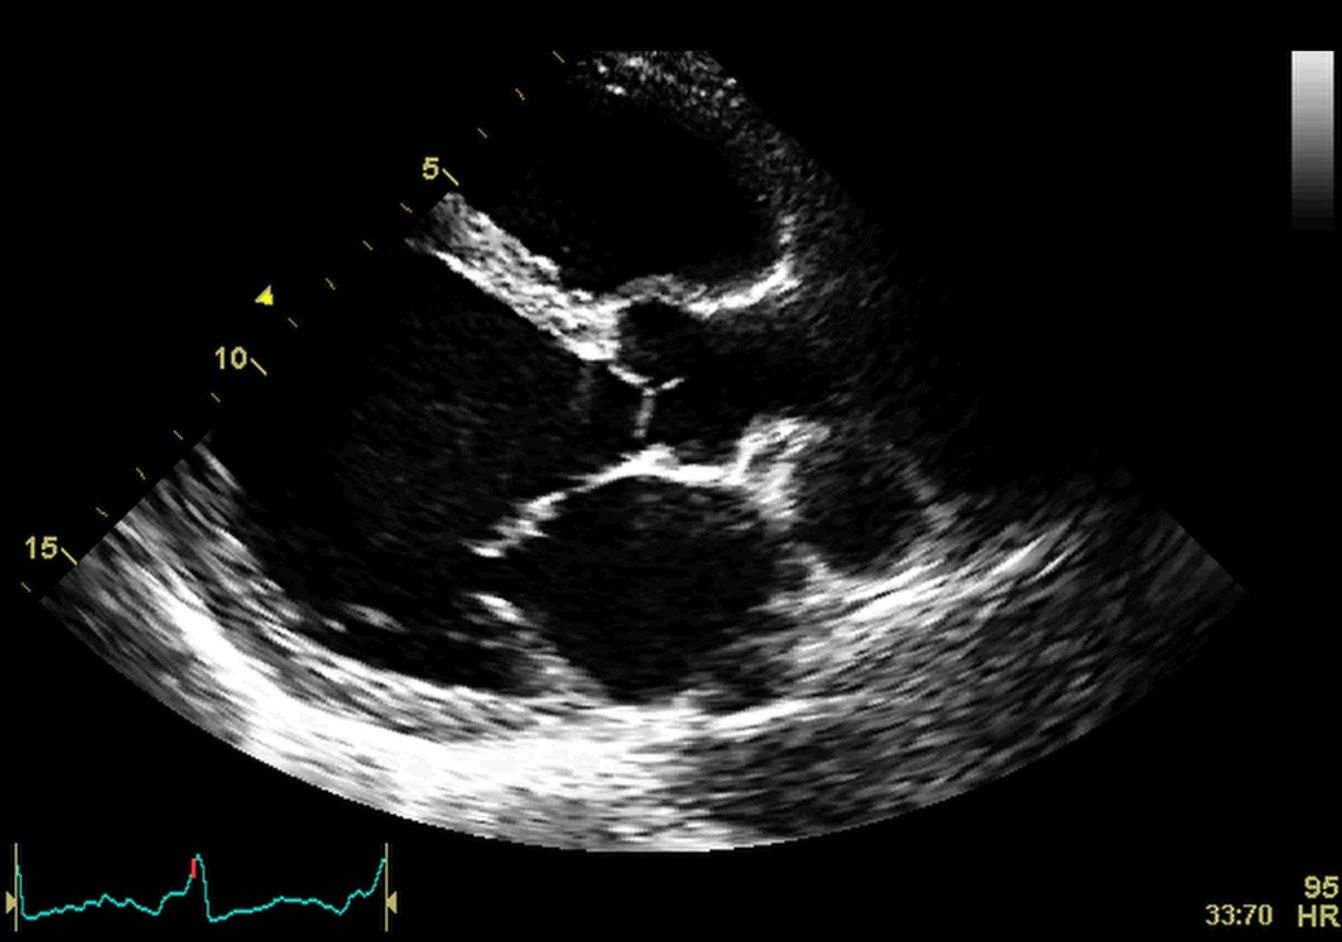

The initial imaging evaluation comprises of two main 2D echocardiography parameters: left ventricle ejection fraction (LVEF) less than 40% or fractional shortening less than 25% [6]. However, the comprehensive diagnosis of DCM should consider aspects of the clinical presentation, patient examination and other test results. Dilatation of the LV, especially end-diastolic and end-systolic transverse diameter enlargement (spherical remodeling), associated with reduced wall thickness, is easily recognized with 2D echocardiography in parasternal long-axis view (See Fig. 1 and Appendix Video 1).

Fig. 1.Echocardiographic aspect of DCM. Parasternal long-axis view showing a dilated left atrium and left ventricle in diastole. An online video of this patient with idiopathic dilated cardiomyopathy is available (Appendix Video 1).